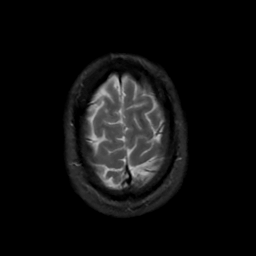

MR Study #6, March 17, 1991 -- Slice #44

[Home][Help][Clinical][Tour 1][Tour 2] Slice 44